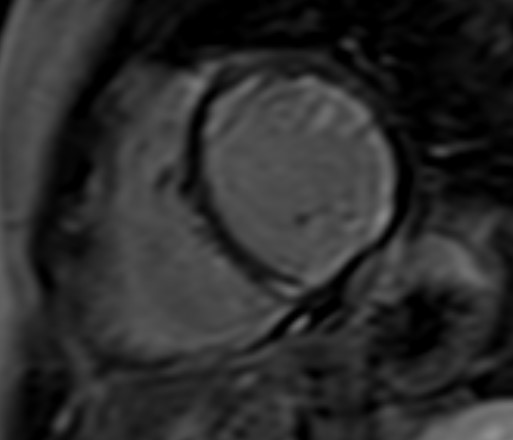

To overcome these limitations, T2 mapping, a parametric image of each voxel, was developed. T2 mapping values are independent of body size and/or heart rate and have good reproducibility [11]; however, they may vary between different scanner types or field strengths and for this reason the definition of individualized normal values for each center is strongly recommended [19, 20]. Increased signal on T2 mapping is an index of myocardial oedema, due to any kind of recent myocardial injury [11] (Fig. 4).

Fig. 4.CMR oedema evaluation using parametric imaging. T2

mapping in patient with polymyositis and ventricular arrhythmias (T2 mapping = 62

msec, normal values